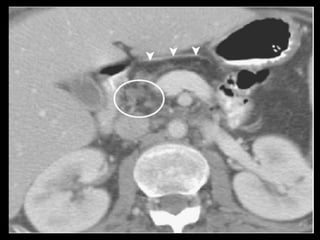

Lobulações da cabeça do pâncreas

A RM e a TCMD mostram densidade e a

intensidade de sinal do pâncreas normais das

lobulações, tanto no exame basal como após a

administração de contraste, acompanhando

paralelamente as características do pâncreas

normal

As margens são bem definidas e não há sinais de

infiltração de estruturas ao redor, dilatação de

ductos biliares ou circundamento vascular.

Classificadas em 3 tipos em relação à artéria

gastroduodenal ou pancreaticoduodenal